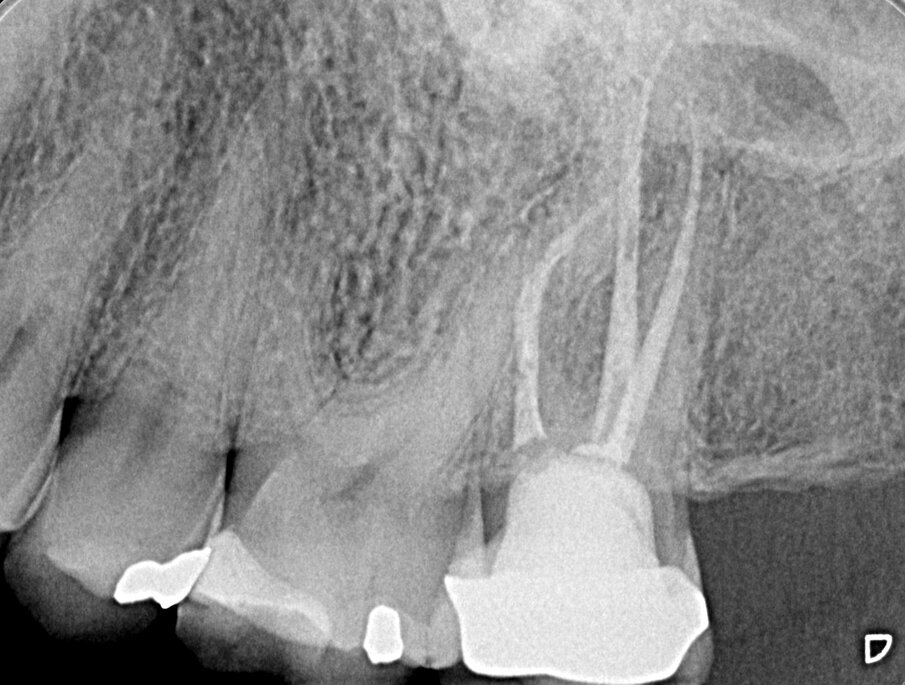

Fig. 1f, 1g - La sezione sagittale mostra ancora meglio le lesioni a carico del primo molare su entrambe le radici vestibolari e le lesioni a carico di entrambe le radici vestibolari del secondo molare, il cui canale MB1 appare completamente vuoto.

Fig. 1h - La sezione assiale mostra le lesioni del primo e del secondo molare, interessanti queste ultime per l’aspetto palatino delle due radici. È ovvio il motivo per cui tali lesioni non erano apprezzabili nella radiografia periapicale.